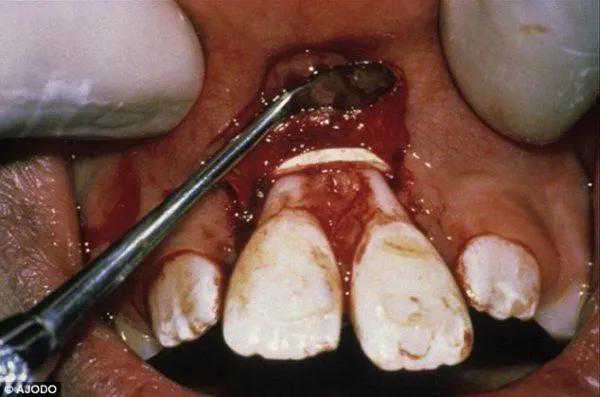

因为橡皮筋的力量很大,很容易破坏牙齿的牙周健康,牙槽骨吸收,牙根吸收,牙齿逐渐松动脱落。更可怕的是橡皮筋会滑脱,如果不及时取出来容易作为一个异物一直感染,甚至一直造成牙槽骨的感染。